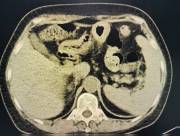

近日,西咸院区移植泌尿外科李智斌团队成功为一名复杂肾病患者同期实施“多囊肾切除+肾上腺肿瘤切除+肾移植术”。此次多术式联合手术,一次性解决了患者终末期肾病、巨大多囊肾及右侧肾上腺肿瘤三大难题,标志着欧美视频

在复杂器官移植领域取得了重要的突破。

该患者病情复杂,巨型多囊肾已对周围脏器造成严重压迫,同时肾上腺肿瘤导致原发性醛固酮增多症需长期口服药物治疗,而异体肾移植更是对手术精度和围术期管理有着极高要求。

手术过程中,李智斌带领团队沉着应对,精准解剖,在切除右侧巨型多囊肾和病变肾上腺之后,快速完成血管吻合,确保移植肾即刻恢复血流。整个手术历时近5小时,术后未出现并发症,现已转入普通病房康复。